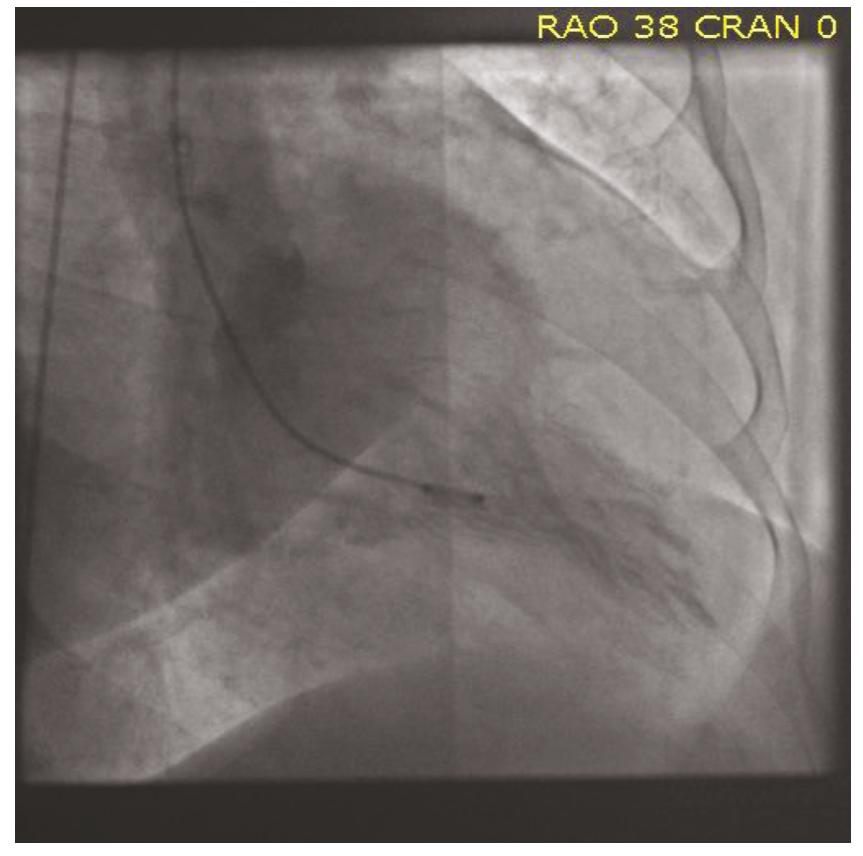

到了这个地步,并没有直接撤台,而是继续做了左室造影(图4),果然左室造影发现心尖部左室腔缩小,随后的心脏超声也明确提示了左室心尖部肥厚,左室腔缩小,左室舒张功能减退,射血分数(EF)值70%。

图4:左室造影提示左室腔变小,心尖肥厚